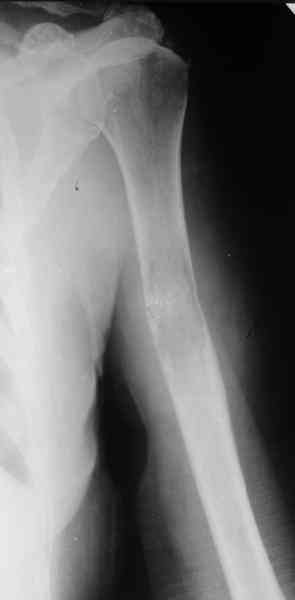

Женщина 53 лет получила патологический перелом правого плеча в феварле, и левого в марте - mts из невыясненного первичного очага.

Сегодня сделали, Fixion диаметром 7,4 мм. Обе пперации продолжались по 7 мин. Картинки в приложении. Наркоз был диприваном, на спонтанном дыхании. По крайней мере, пока довольны хотя бы анестезиологи, похоже, не верили, что управимся меньше, чем за час ;-)

Гвоздик 7,4 расширяется до 11 мм. Не маловато ли, судя по снимкам?